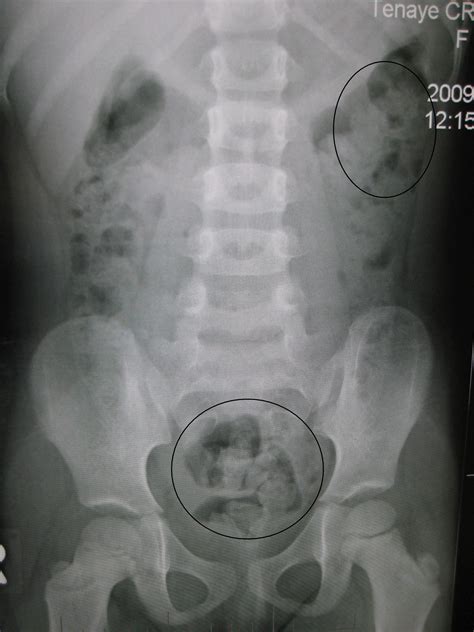

Common Findings in a Normal Abdominal X Ray

A Normal Abdominal X Ray typically reveals the following structures and patterns:

• Gas patterns in the stomach and intestines

• Clear outlines of the liver, spleen, and kidneys

• No signs of obstruction or perforation

• No evidence of foreign bodies

These findings indicate that the abdominal organs are functioning normally and there are no immediate concerns.